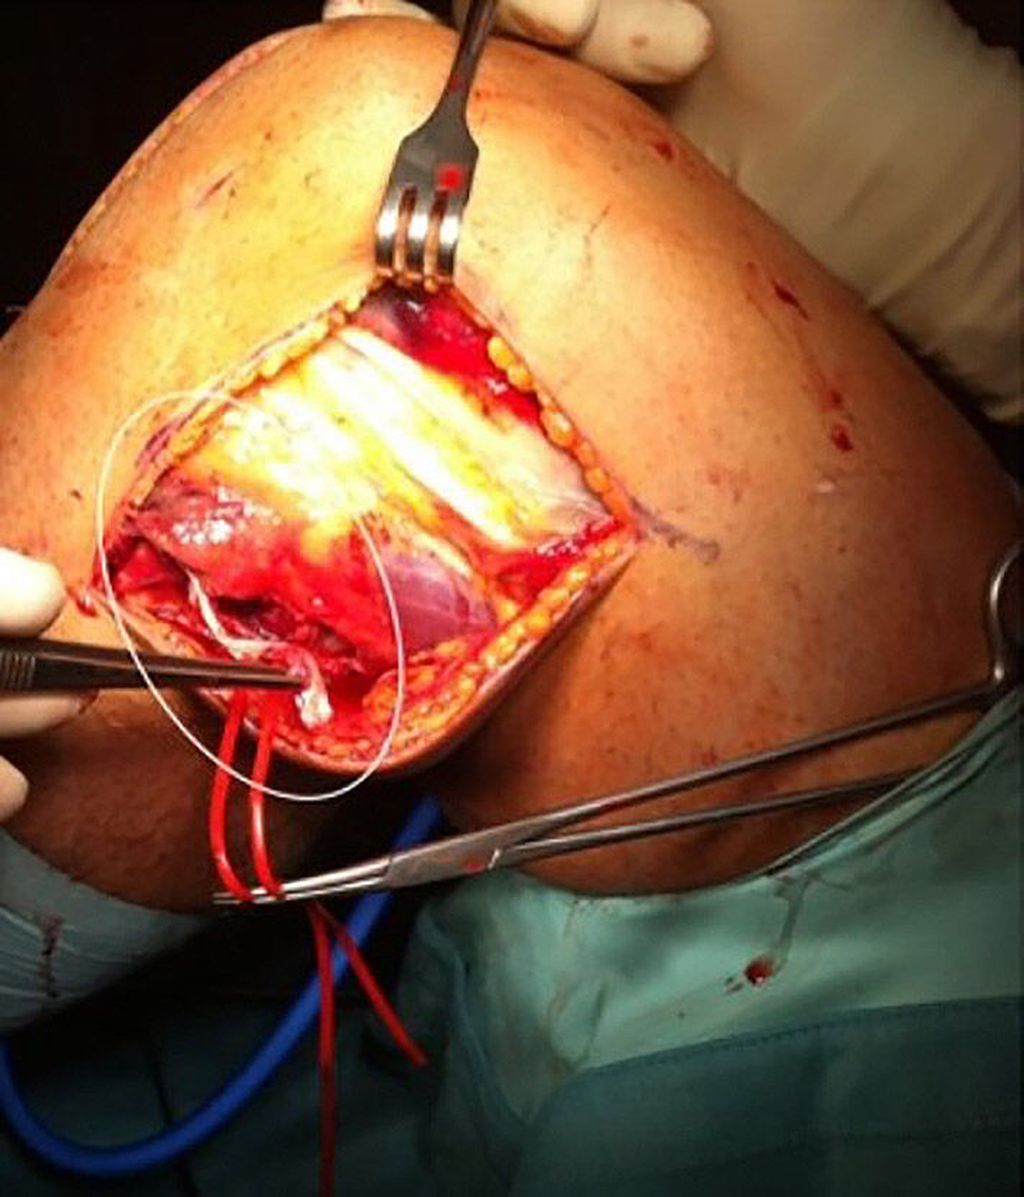

Eine MRT-Kontrolle nach 18 Monaten zeigte ein unauffälliges Transplantat (Abb. 4). Bei der postoperativen 2-Jahres-Kontrolle hatte der Patient keine Instabilität, er konnte wieder auf Leistungsniveau Fußball spielen (Abb. 5).

Abb. 4: Postoperative MRT-Kontrolle nach 18 Monaten, die ein unauffälliges und stabiles Semitendinosus-Gracilis-Transplantat in der Larson-Technik zeigt